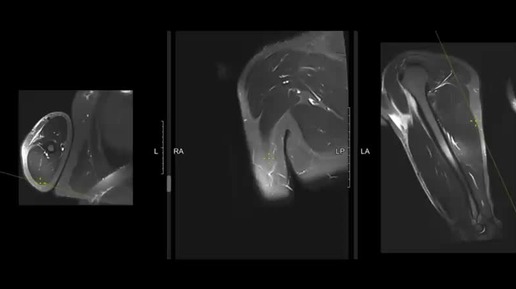

МРТ мягких тканей конечности одной области